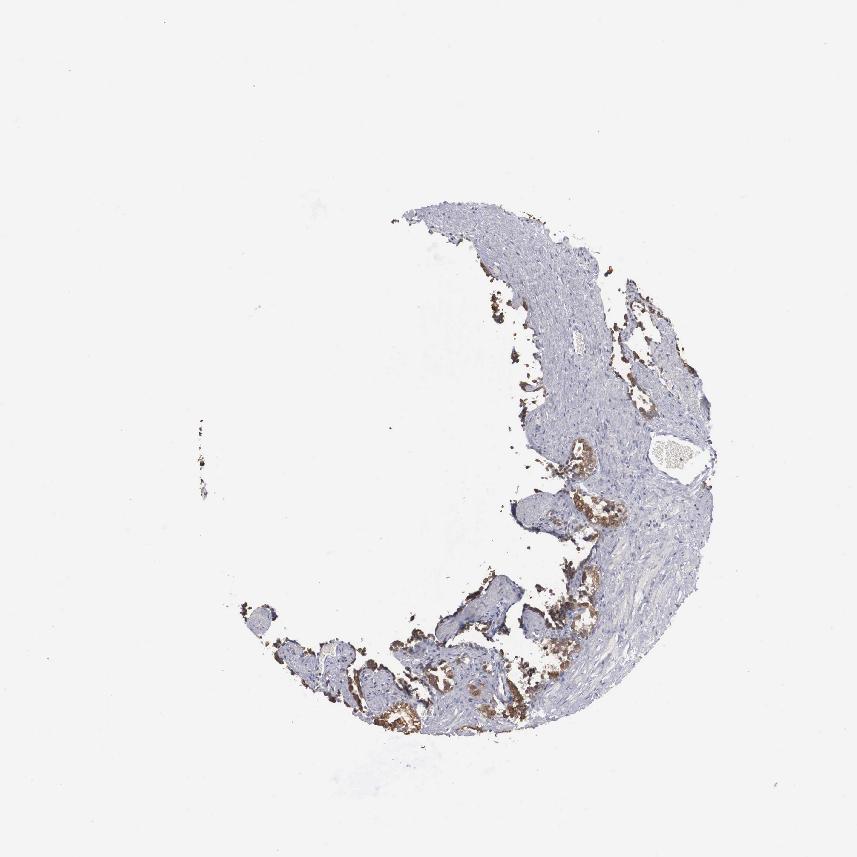

SEMINAL VESICLE - Antibody stainingi

Antibody staining in the annotated cell types in the current human tissue is reported as not detected, low, medium, or high, based on conventional immunohistochemistry profiling in selected tissues. This score is based on the combination of the staining intensity and fraction of stained cells.

Each image is clickable and will lead to virtual microscopy that enables deeper exploration of all samples and also displays staining intensity scores, fraction scores and subcellular localization as well as patient and tissue information for each sample.

Antibody HPA000813

Glandular cells Low